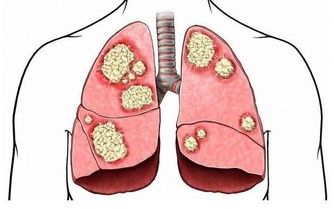

白血病通常是指患者體內的白細胞發生了異變,影響到各個器官和組織,並且妨礙正常造血。白血病有急性和慢性之分,急性白血病患者的病情惡化速度非常快,如果無法立即接受治療,很有可能在短短幾週內便導致患者死亡。

淋巴細胞也是白細胞的一種,能夠抵抗感染。如果淋巴細胞發生癌變,那麼會誘發淋巴瘤。血液科專家表示,淋巴瘤患者體內的淋巴細胞會發現許多變化,例如分裂方式不同於健康細胞,或者是在應該死亡時依舊活躍在患者體內,無法代謝。

多發性骨髓瘤是一類會抑制人體生產出健康血細胞的癌症。臨床研究表明,多發性骨髓瘤會損傷到患者身體的多個部位,常見的是脊椎、顱骨、骨盆,以及肋骨。在發病初期,患者可能不會出現任何異常症狀。